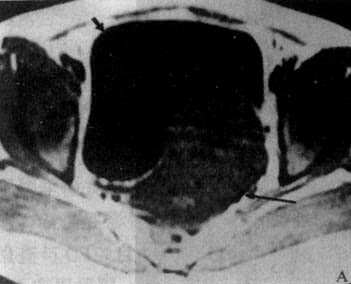

子宫体在CT上易于识别,显示为横置的密度较高的梭形影像,CT值40~80Hu,宫体中央密度可略低。子宫大小受年龄和生理状态的影响,一般成人前后径为1.5~3cm,左右径为3~5cm,老年人子宫较小。膀胱充盈程度也影响子宫的大小。子宫前方为膀胱,呈液性低密度;后方为直肠,内常有气体。膀胱、子宫、直肠之间常有肠袢存在。宫颈在宫体下方层面,呈卵圆形软组织影。卵巢位于子宫侧壁和臼内壁之间,正常大小时CT常不见。增强扫描,子宫密度均匀增加,膀胱内造影剂为高密度,盆腔内血管输尿管显示为高密度,易于识别(图4-5-5)。

图4-5-5 女性盆腔正常CT表现

子宫呈横行的梭形软组织影(↓),其前方为膀胱(B)

其后方、骶骨之前为直肠(R)